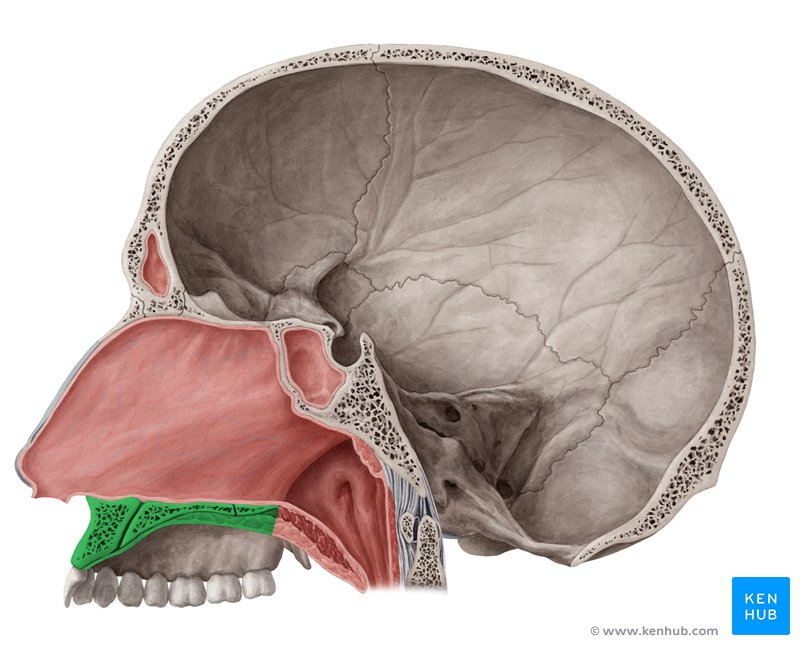

Hard palate

Soft palate

Uvula

Palatoglossal arch

Palatine tonsils

green highlight